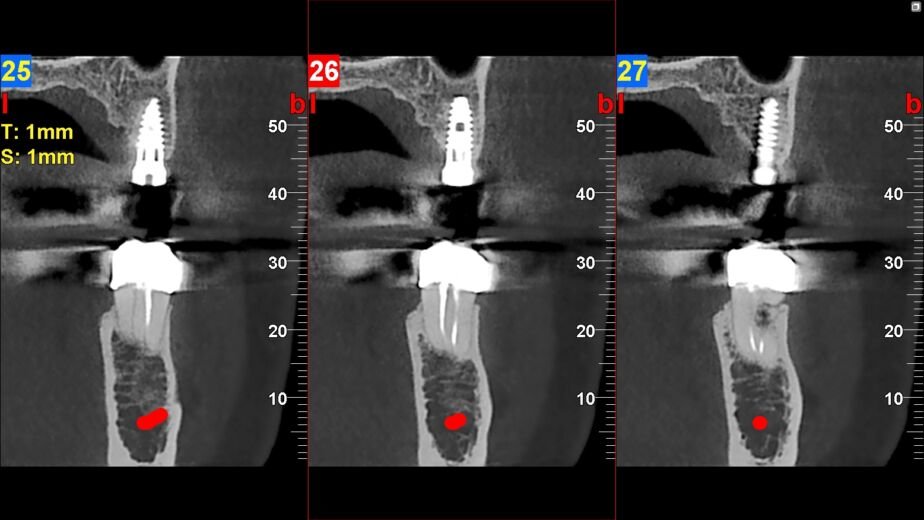

Imaginen la salud bucal como un jardín. Las malas hierbas pequeñas son fáciles de arrancar. Si se dejan crecer, sus raíces se extienden y pueden dañar todo el jardín. De igual forma, las pequeñas anomalías en la región maxilofacial, como quistes incipientes, infecciones ocultas o fracturas hairline, son más manejables si se detectan pronto. Un TAC macizofacial puede identificar estas «malas hierbas» antes de que se conviertan en un problema mayor. Permite identificar problemas óseos, como la pérdida de densidad ósea, o anomalías en la anatomía de los senos paranasales que podrían afectar la salud bucal.

La odontología moderna busca soluciones proactivas. Un TAC macizofacial ofrece una visión clara de la disposición de nervios, vasos y estructuras óseas. Esta información es crucial para planificar procedimientos como extracciones de muelas del juicio impactadas, implantes dentales o cirugías ortognáticas. Al tener un «mapa» preciso, el cirujano puede evitar daños a estructuras vitales, reduciendo el riesgo de complicaciones como parestesias (adormecimiento) o hemorragias. Sin esta herramienta, algunos procedimientos serían un viaje a ciegas.

Los huesos de la cara y la mandíbula son el soporte de la dentadura y la estructura facial. Un TAC macizofacial evalúa la densidad y calidad del hueso, información crítica para la colocación de implantes dentales, que requieren una base ósea robusta. También permite detectar enfermedades óseas metabólicas o tumores que afectan la estructura ósea, antes de que causen daños irreversibles o comprometan la función masticatoria y estética.

Enfermedades Periodontales Avanzadas y Pérdida Ósea

Las enfermedades periodontales, si no se controlan, pueden llevar a la pérdida de hueso alrededor de los dientes, lo que a su vez causa la movilidad y eventual pérdida dental. Un TAC macizofacial permite cuantificar la pérdida ósea con gran precisión, mostrando el patrón de reabsorción ósea tridimensionalmente. Esta información es crucial para evaluar el pronóstico de los dientes y planificar tratamientos periodontales o, si es necesario, la colocación de implantes.

Quistes y Tumores

La detección temprana de quistes o tumores en la región maxilofacial es fundamental para un buen pronóstico. Estas lesiones, a menudo asintomáticas en sus etapas iniciales, pueden expandirse y destruir hueso, desplazar dientes o invadir estructuras adyacentes. Un TAC macizofacial proporciona una imagen clara de su tamaño, ubicación, relación con estructuras vitales y características internas, lo que ayuda a determinar si la lesión es benigna o maligna y guiar la biopsia o el plan quirúrgico.

Numerosos casos clínicos ilustran la importancia del TAC macizofacial. Por ejemplo, un paciente con dolor facial inespecífico, donde las radiografías convencionales no revelaban nada, pudo obtener un diagnóstico de sinusitis maxilar crónica oculta gracias a un TAOtro ejemplo es la planificación de implantes en pacientes con poco hueso, donde el TAC permite identificar las zonas con suficiente densidad ósea y evitar estructuras nerviosas o sinusales, asegurando el éxito del tratamiento. En la detección de pequeños tumores ocultos, el TAC ha sido crucial para su identificación temprana, permitiendo una intervención oportuna y salvando la vida del paciente.